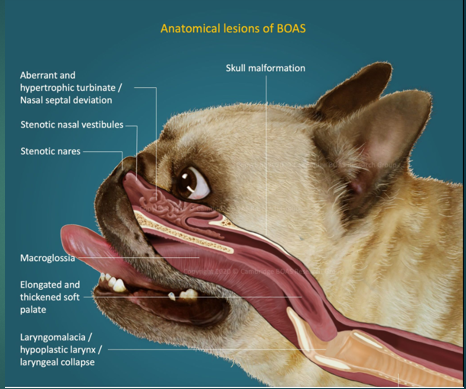

Stenotic nares

Narrowing of the nasal passages, this increases resistance, making breathing in and out more difficult for the paitent

Oversized tongue

Tongue is too big for their moth, can push on soft plate

Elongated soft palate

Effects the epiglottis so can aspirate more easily

Hyperplastic larynx

Overgrowth of soft tissue in the larynx, leading to obstruction

Hypoplastic trachea

Trachea is narrower

Brachycephalic obstructive airway syndrome

The problems we see in these breeds are the consequences of trying to move air with all this increased resistance. To breathe they need to move O2 through the resp tract to the lungs, these issues with the soft tissues that we’ve highlighted cause resistance to air flow, this then increases Resp effort and rate to get more air in, this increases the negative pressure which makes the issue worse – negative pressure caused by them trying to overcome the resistance means that we get more resistance, more swelling of soft tissues and thus more negative pressure. We will often see abdominal effort with BOAS breathing.

Brachycephalic breeds are prone to becoming hypoxic and overheating ..

When panting air moves over mms and evaporates loose heat – in these animals not as effective, so owners have to be very careful in the heat not to cause heat exhaustion and collapse.